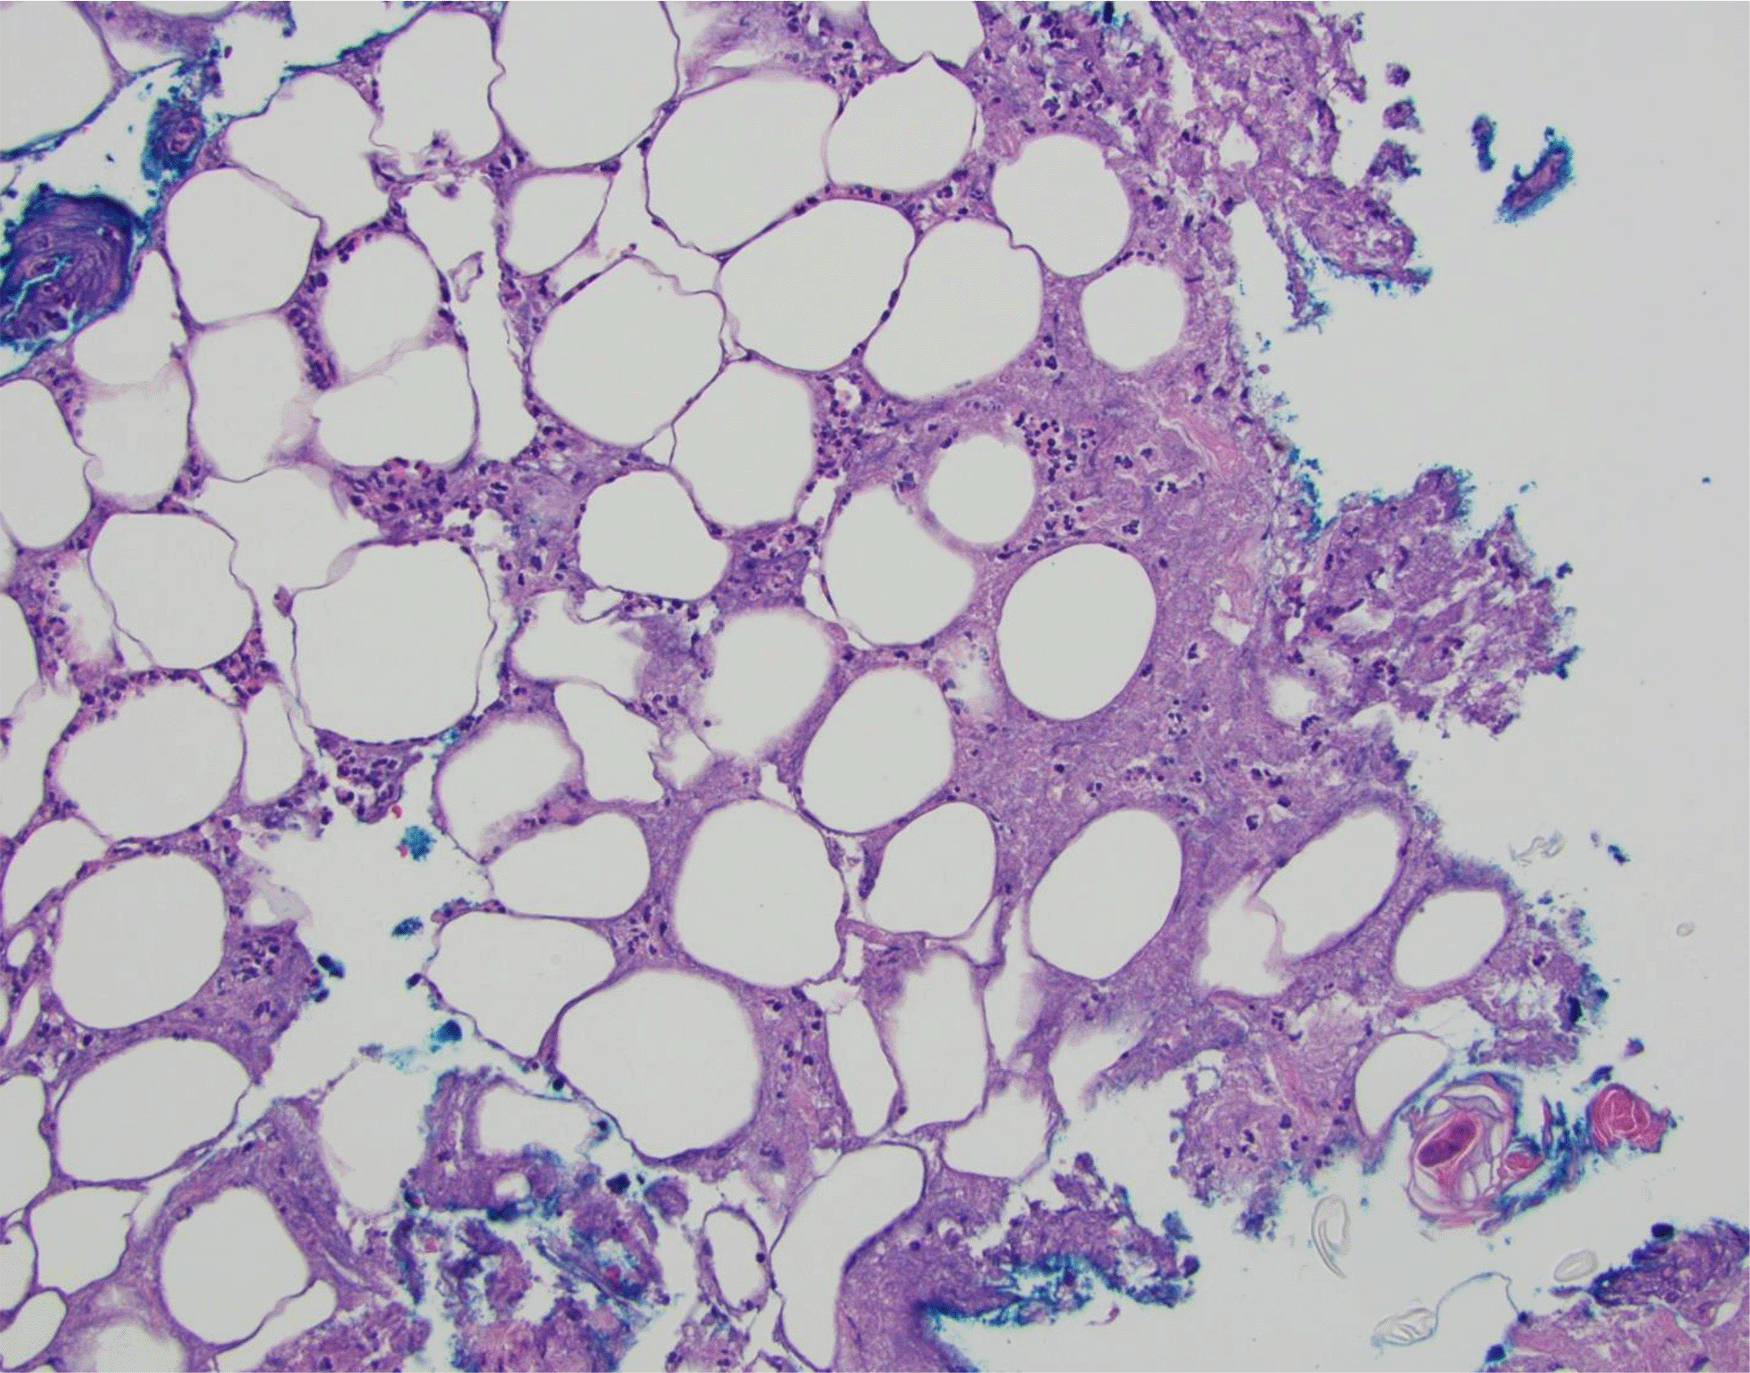

Empiric antibiotic therapy began with vancomycin (60 mg/kg/day intravenously divided every 6 hours for 3 days) and ceftriaxone (75 mg/kg/day intravenously every 24 hours for 3 days) which was then transitioned to cefazolin (100 mg/kg/day intravenously divided every 8 hours for 7 days), clindamycin (30 mg/kg/day intravenously divided every 8 hours for 7 days), amoxicillin-clavulanate (50 mg/kg/day orally divided every 12 hours for 4 days), and then to linezolid (30 mg/kg/day intravenously divided every 8 hours for 6 days) due to a lack of clinical and laboratory improvement. A lesion on her back was biopsied and demonstrated acute suppurative panniculitis and suppurative necrosis (Figure 2). Cultures were obtained with growth of P. aeruginosa and a 3-week course of cefepime (150 mg/kg/day intravenously divided every 8 hours) for SSTI was completed. Clinical and laboratory improvement occurred as demonstrated by an ESR 57 mm/hr (normal range: 0-20) and CRP <5 mg/L (normal range: 0-10). The patient was discharged while awaiting results of a workup for an inborn error of immunity.

Skin punch biopsy demonstrates acute suppurative panniculitis with suppurative necrosis (20×, Hematoxylin and Eosin).